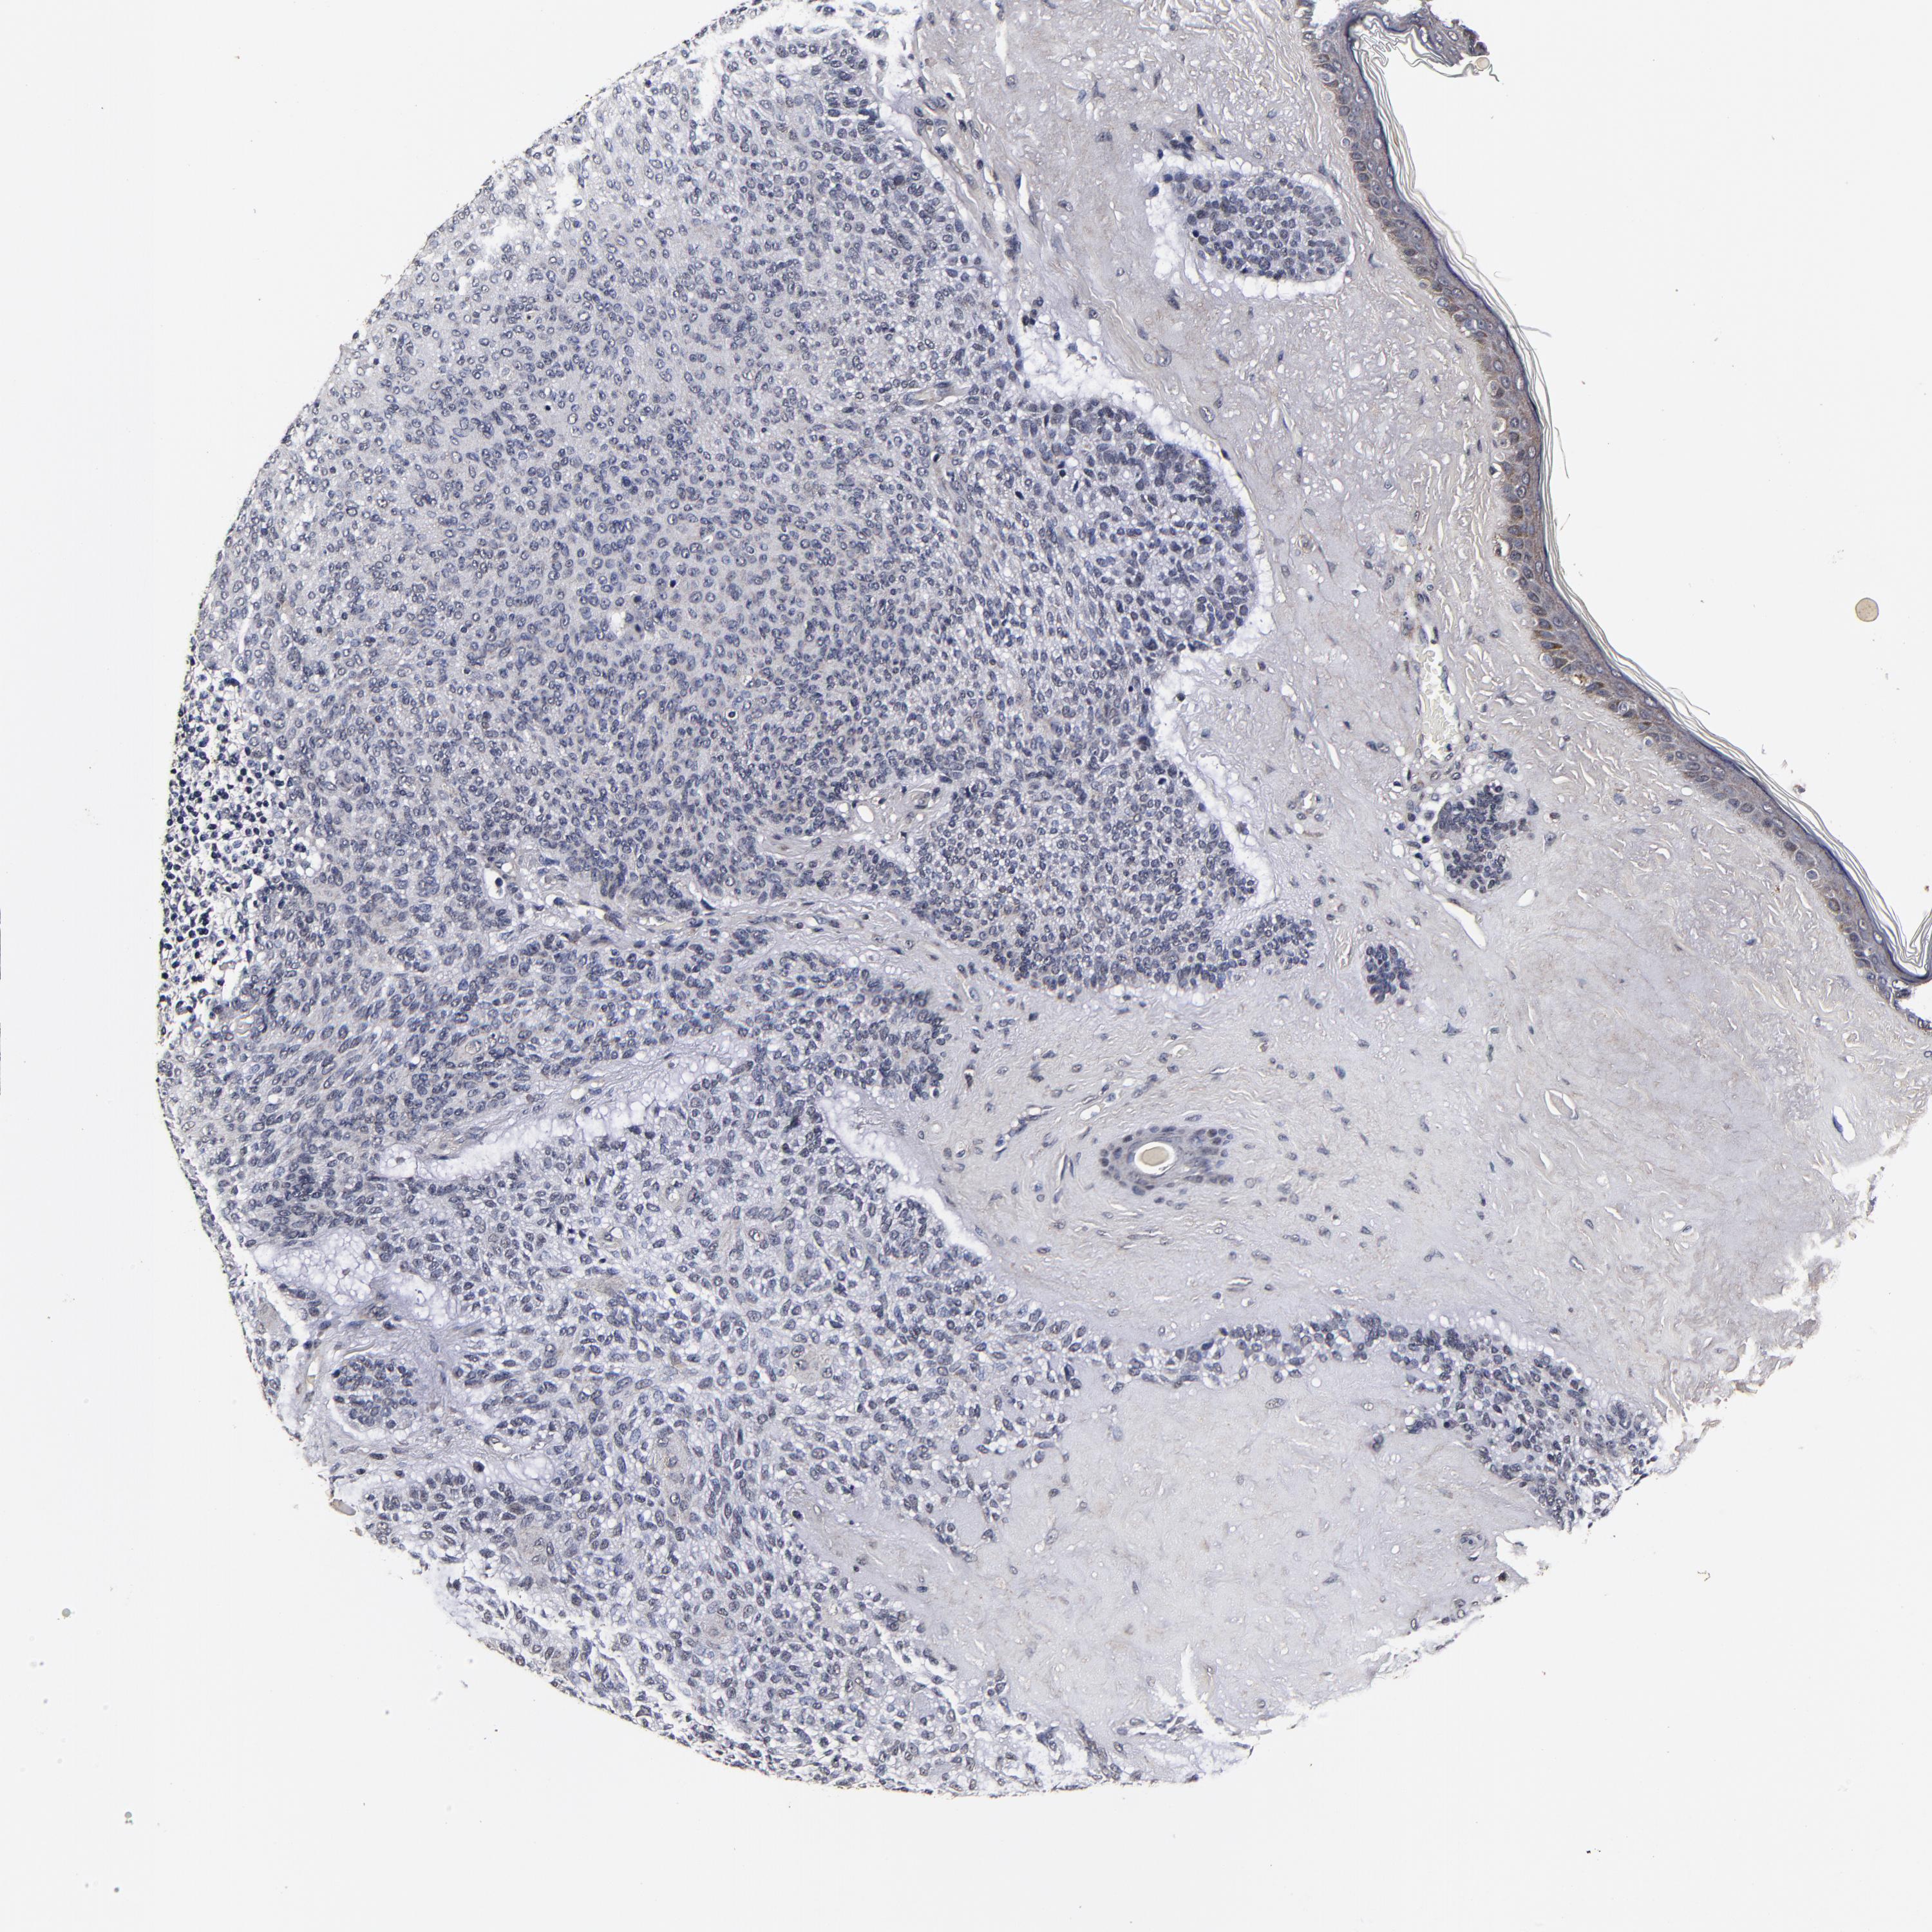

SKIN CANCER - Protein expressioni

A mouse-over function shows sample information and annotation data. Click on an image to view it in a full screen mode. Samples can be filtered based on level of antibody staining by selecting one or several of the following categories: high, medium, low and not detected. The assay and annotation is described here.

Antibody stainingi

Antibody staining in the annotated cell types in the current human tissue is reported as not detected, low, medium, or high, based on conventional immunohistochemistry profiling in selected tissues. This score is based on the combination of the staining intensity and fraction of stained cells.

Each image is clickable and will lead to virtual microscopy that enables deeper exploration of all samples and also displays staining intensity scores, fraction scores and subcellular localization as well as patient and tissue information for each sample.

Antibody HPA040390

Antibody CAB002611

Staining

High

Medium

Low

Not detected

Intensity

Strong

Moderate

Weak

Negative

Quantity

>75%

75%-25%

<25%

None

Location

Nuclear

Cytoplasmic/membranous

Cytoplasmic/membranous,nuclear

Squamous cell carcinoma, metastatic, NOS

Squamous cell carcinoma, NOS